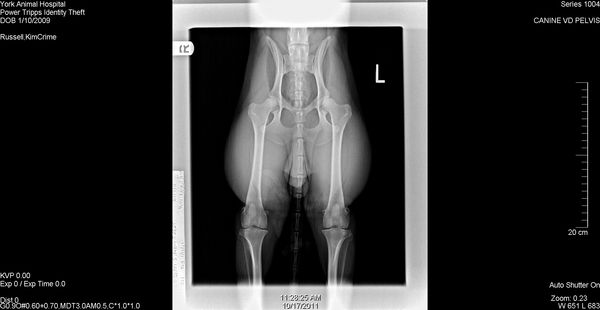

CEA DNA Normal, CERF Normal, OFA Excellent, TNS Normal

2009/1/10AKC DN23731101 CEA DNA Normal by parentage, CERF Normal, OFA Excellent, TNS Normal